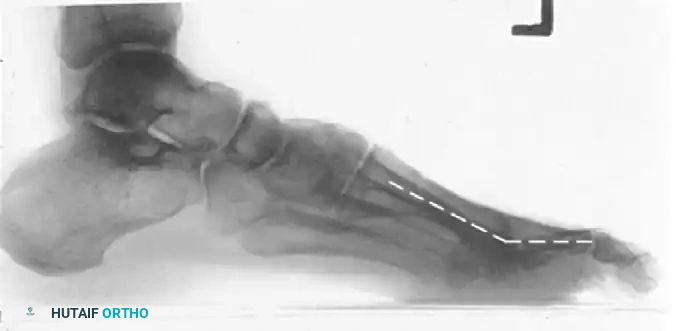

Image

Postoperative lateral radiograph of a first MTP arthrodesis. Note the hardware placement and the preservation of the weight-bearing arch.

Postoperative lateral radiograph with dashed lines illustrating the optimal angle of arthrodesis, ensuring the hallux clears the ground slightly during the swing phase while providing a stable platform during stance.